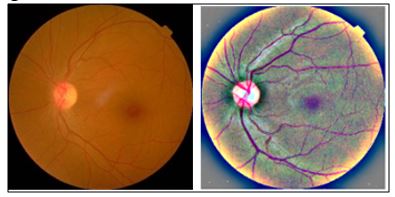

Deep Learning Based Identification and Categorization of Various Phases of Diabetic Retinopathy

Reem Jawed Unar, Muhammad Ahsan Ansari, Syed Muhammad Shehram Shah, Jawed Unar, Khair Muhammad Unar, Sammer Zai

772-784